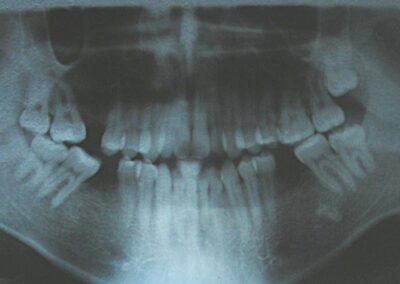

Cephalometric analysis confirmed a vertical skeletal discrepancy, consistent with a skeletal-based anterior open bite. The initial treatment plan involved a combined orthodontic-surgical approach, including bimaxillary surgery: Le Fort I impaction osteotomy with preliminary surgically assisted maxillary expansion and bilateral sagittal split osteotomy (BSSO), with possible genioplasty.

The patient presented with an anterior open bite, characterized by the absence of vertical overlap between the upper and lower incisors, and bilateral posterior crossbite. Extraoral examination revealed a vertically long facial pattern with an increased lower third of the face. The profile is convex with a retruded chin, indicating sagittal and vertical skeletal imbalances. We find also the inclined bipupillary line, which corresponds to facial asymmetries and altered occlusal plane.

Absent #16, #36 and #46 , No Angle molar relationship . Projection of canines axes in class II relationship . Anterior open bite: Over Bite – 8 mm). Bilateral posterior crossbite: Involvement of upper posterior sectors with inverted buccal-lingual relationship. Moderate Crowding at the level of the upper and lower incisors. Acceptable Oral Hygiene with no periodontal issues

Cephalometric diagnosis